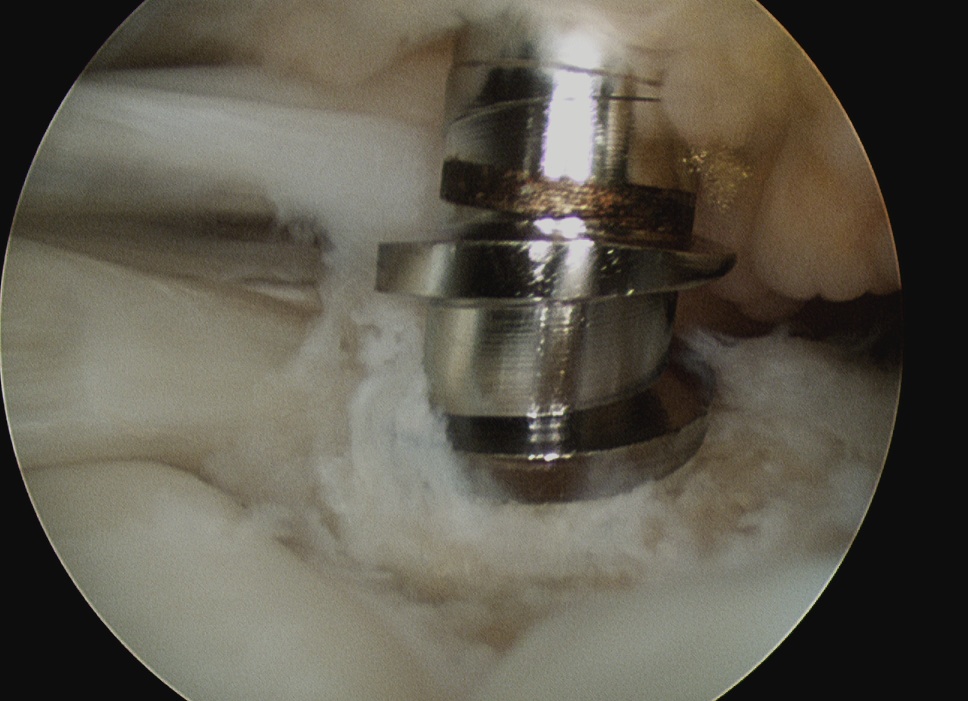

Place medial row anchors

- anterior first

- insert 18 G spinal needle and ensure good angle

- just medial to articular cartilage

- stab incision

- insert 5 mm anchor